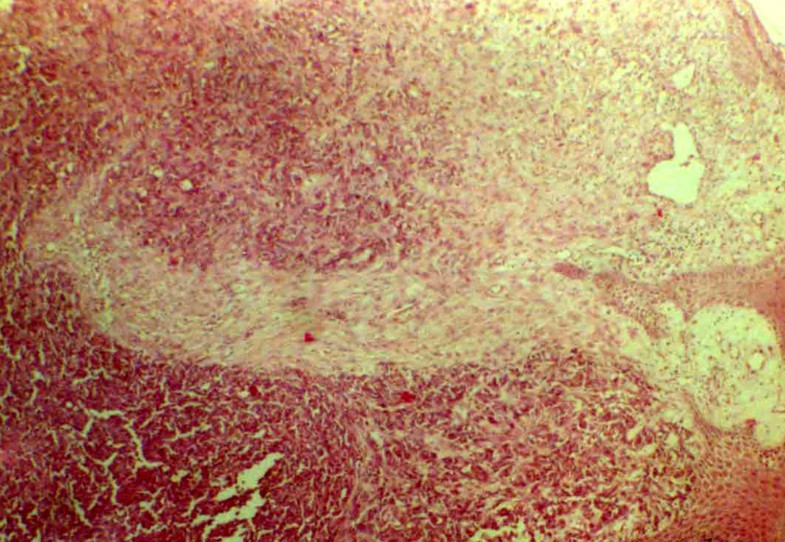

Merkel cell carcinoma — codes and concepts. Merkel cells were first described in the late 1800s by a german doctor named friedrich merkel. Mccs are dermally based tumors composed of small uniform round blue cells arranged in anastomosing cords, bands and clusters. Approved for advanced merkel cell carcinoma (a kind of skin cancer). It starts when cells in the skin called merkel cells start to grow out of control. Merkel cell carcinoma (mcc) is a rare and aggressive skin cancer occurring in about 3 people per 1,000,000 members of the population. Merkel cell carcinoma is a highly aggressive primary cutaneous neuroendocrine carcinoma primarily affecting elderly and immunosuppressed individuals. Merkel cell carcinoma treatment options include surgery, radiation therapy, and chemotherapy. Merkel cell carcinoma (mcc) gets its name because these skin cancer cells resemble merkel cells, which are located in the top layer of skin. Has a tendency to spread from the skin to another part of the body. Merkel cell carcinoma typically occurs in elderly fair skinned individuals in the seventh and eighth decades of life, with a slight male predilection. A fit 80 year old woman presents with a merkel cell carcinoma of the middle of the right cheek, 8mm in maximal transverse diameter. Although merkel cell carcinoma can affect any part of the skin, it is most common on skin that has been chronically exposed to sunlight (for example, the face.

We present two cases of primary merkel cell carcinoma, one on the buccal mucosa and the other on the lower lip, and discuss the salient. Merkel cell carcinoma (mcc) is an uncommon relatively aggressive neuroendocrine dermal neoplasm first described in 1972 as a tumor of the sun exposed skin. The reported incidence of mcc has more than tripled in the past 20 years1. Updated by a/prof amanda oakley, hamilton, new zealand. Figure 1 primary mcc, chin.